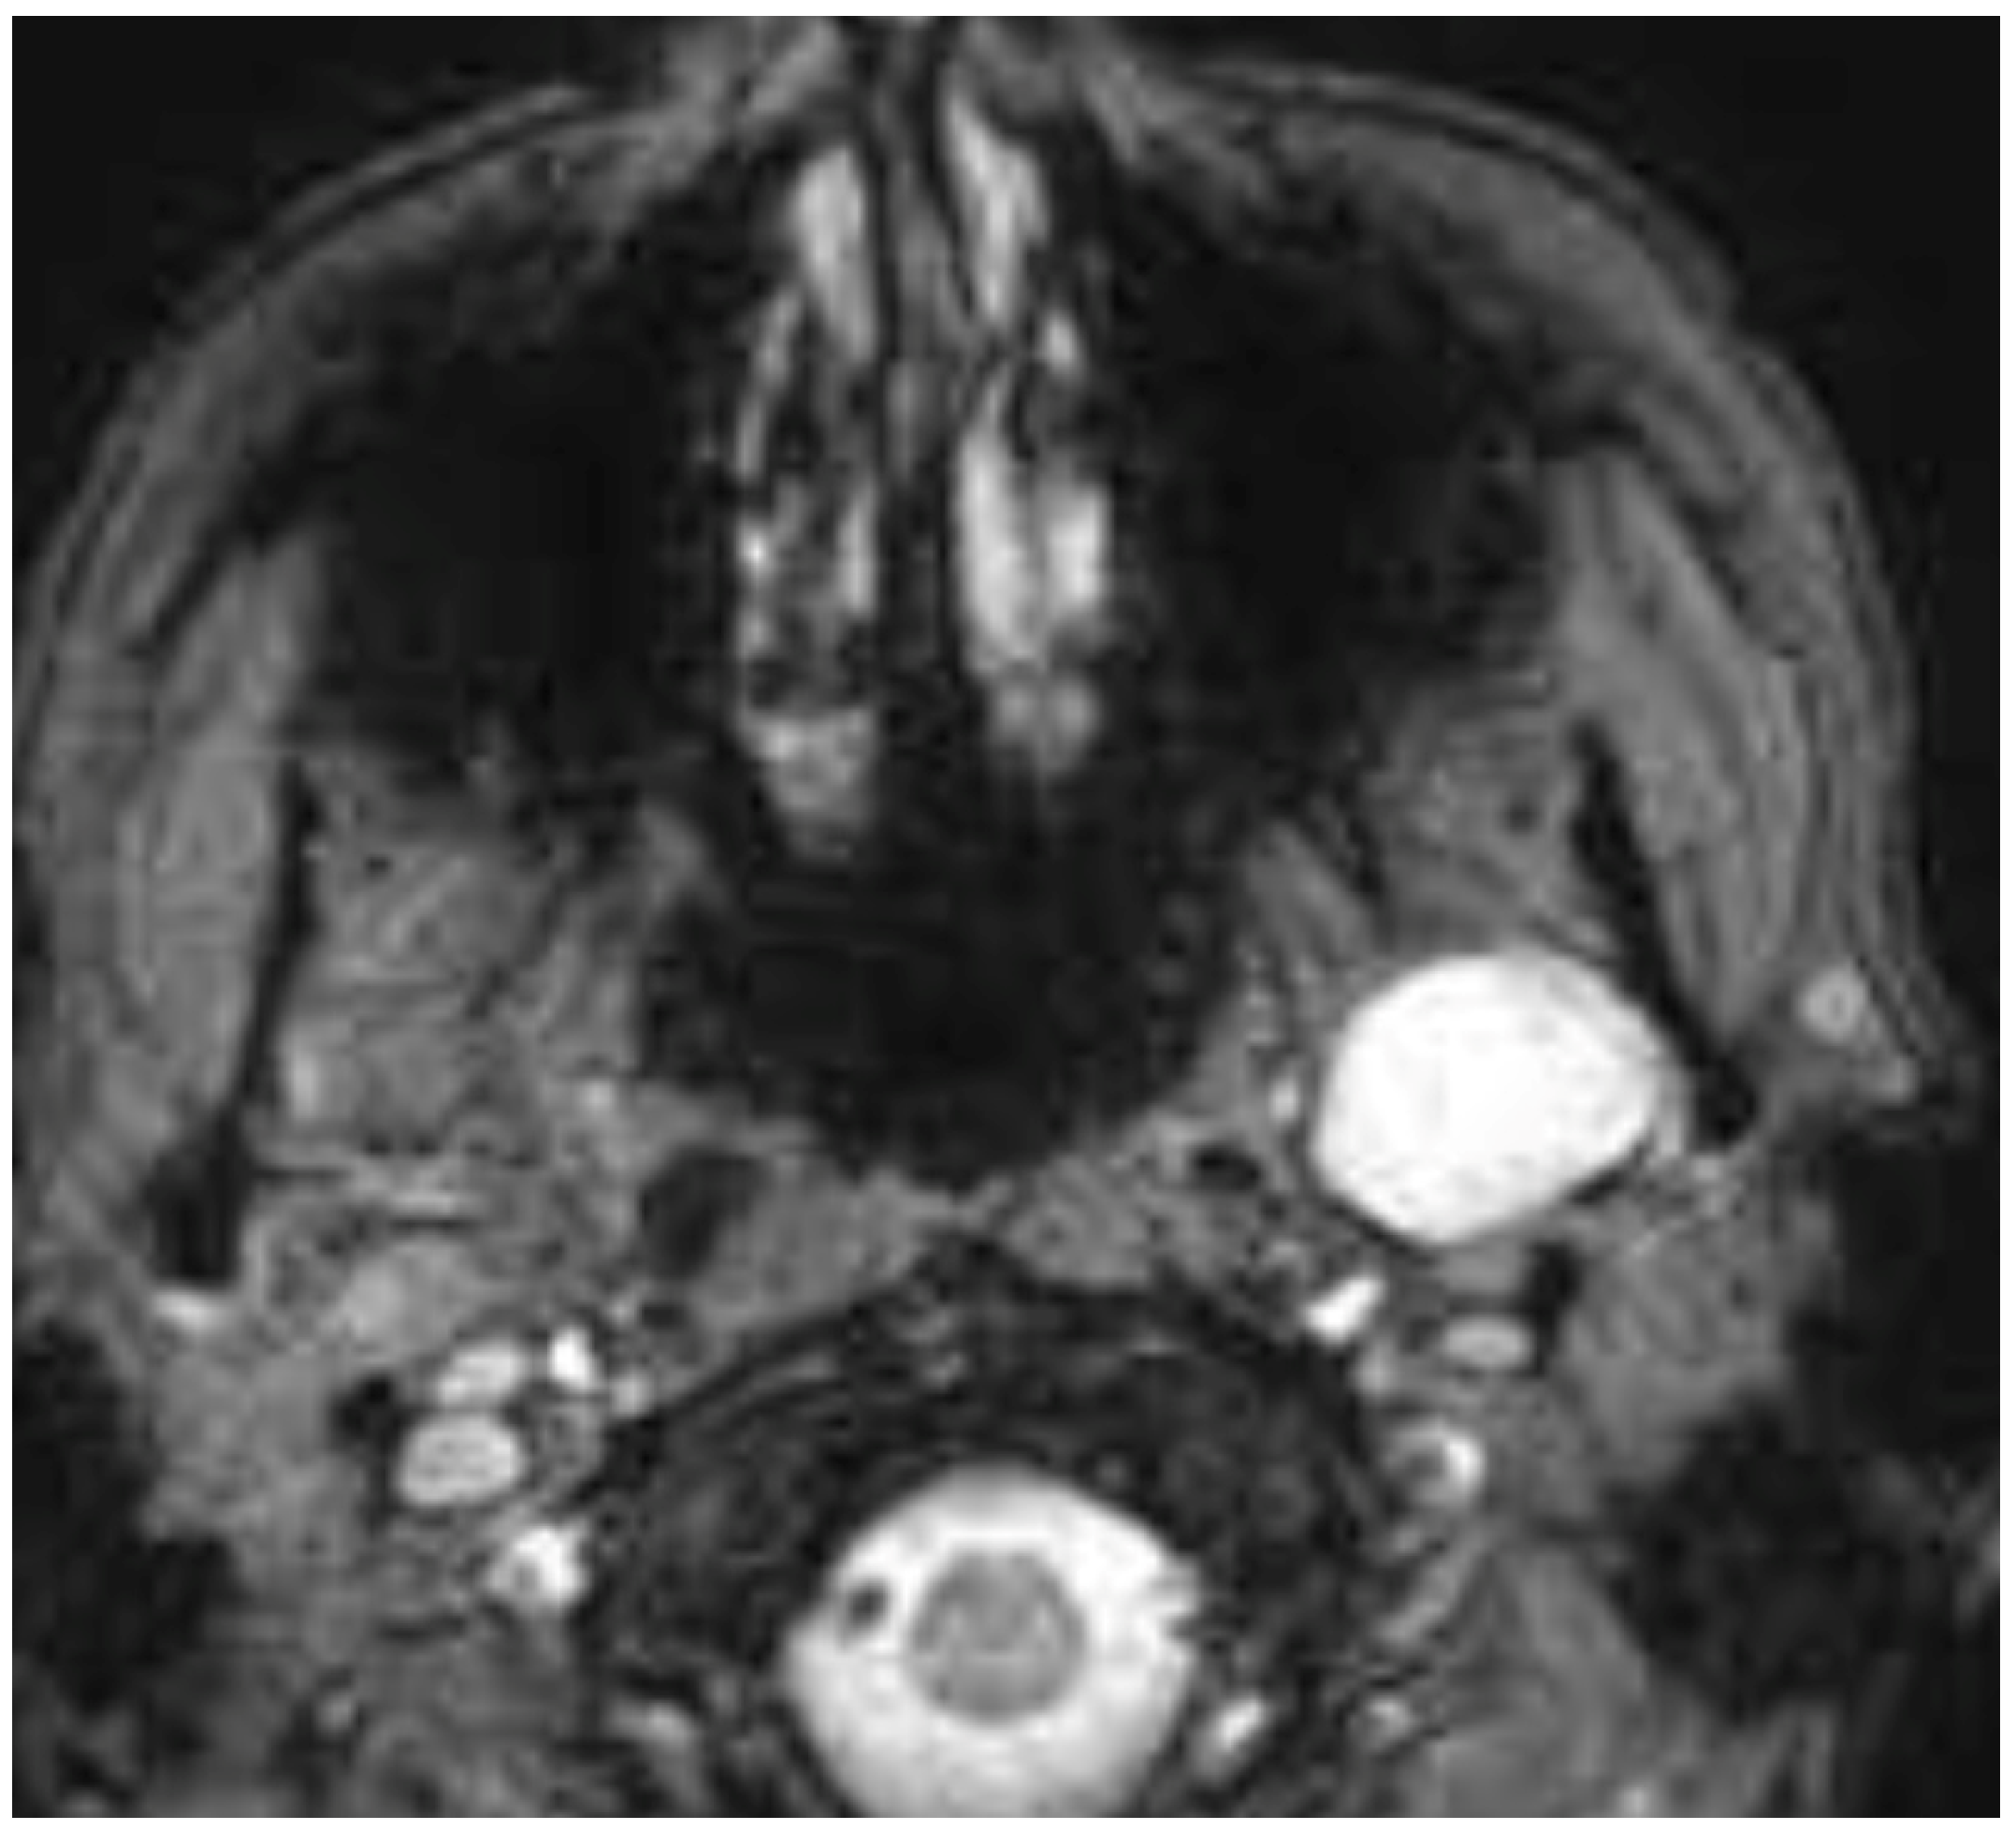

The treatment of PPS pathology represents a territory where both transoral approaches have been proposed, even as alternatives to classic open transcervical or transcervical–transparotid approaches [1,5]. Numerous authors in recent years have described the safety and efficacy of these transoral techniques, demonstrating favorable outcomes in terms of postoperative pain, length of hospital stay, and aesthetic results compared to traditional external approaches [1,5]. Our presented case series, as highlighted in the summary table, corroborates these findings. Specifically, in our cohort, postoperative pain was never significant (managed with as-needed paracetamol when required), hospitalization was brief, and no patient necessitated an external incision, offering advantages in terms of both postoperative recovery and aesthetic outcomes. This shift towards the selection of a transoral corridor is gaining momentum; however, it is crucial to emphasize several aspects. The meticulous evaluation of the patient and the tumor is paramount when considering a transoral approach [1,5,6,7]. A thorough clinical and radiological assessment is essential, particularly to evaluate the benign or malignant characteristics of the lesion, its vascularity in the case of vascular lesions, and its relationship with major neck vessels, which could lead to critically challenging management issues if these evaluations are not diligently performed [1,5,6,7]. Many case series highlight that tumors removed via these approaches are predominantly benign, non-vascular, and encapsulated lesions, such as pleomorphic adenomas and schwannomas. Malignant tumors, where open approaches are often more appropriate, and vascular tumors like paragangliomas, due to the high risk of intraoperative hemorrhage and subsequent difficult management via a transoral route, are typically excluded from these techniques [1,5]. Consequently, magnetic resonance imaging (MRI) with contrast enhancement frequently serves as the primary imaging modality to confirm clinical assessment and guide the decision-making process for selecting suitable candidates for transoral surgery [1,5]. In this presented multicentric case series, all benign and encapsulated lesions removed via the transoral route exhibited a favorable pattern of major vessel displacement. Specifically, the seven true PPS tumors, comprising five pleomorphic adenomas originating from ectopic salivary tissue, minor salivary glands, and the deep lobe of the parotid gland, consistently demonstrated a posterior displacement of the major neck vessels and an anteromedial displacement pattern of the parapharyngeal fat, a characteristic typically associated with benign lesions of the true PPS [1,5]. Figure 3 illustrates a pleomorphic adenoma from our case series, originating from accessory salivary glands of the true PPS, demonstrating this characteristic pattern of posterior displacement.

Figure 3. Pleomorphic adenoma originating from the true PPS with posterior major vessels’ dislocation.